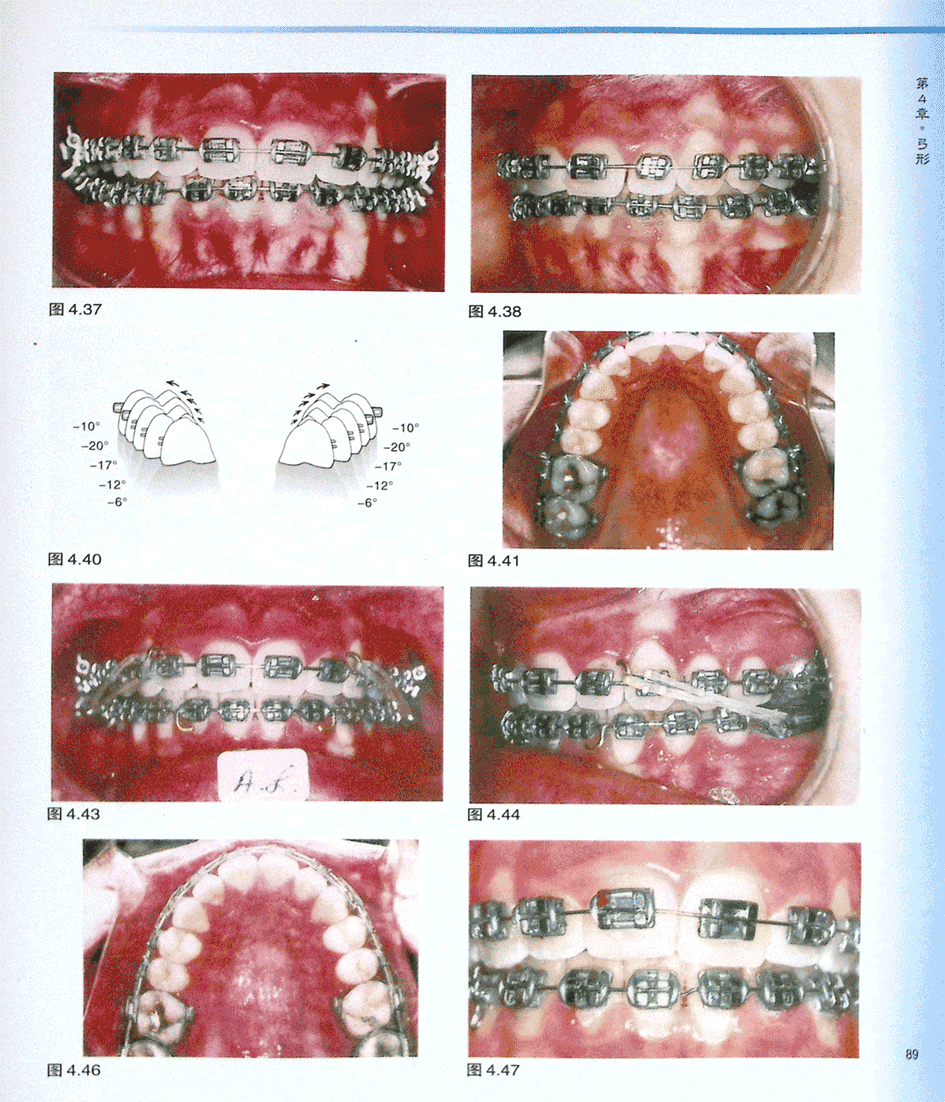

病例AL(二)